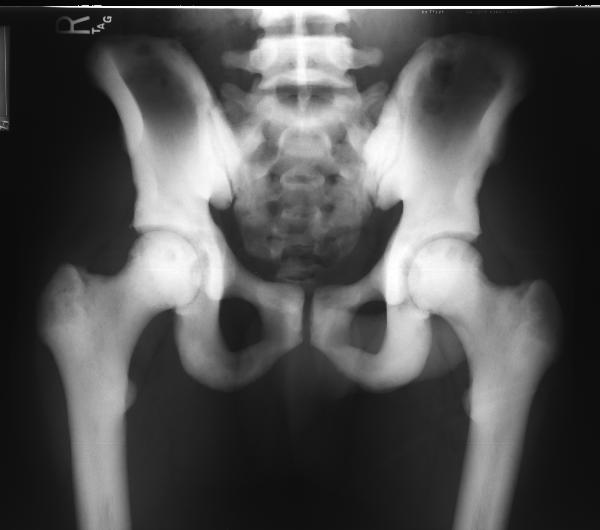

osteopetrosis2.jpg (14997 bytes)osteopetrosis4.jpg (20981 bytes)

After reviewing the above x-rays of this 40 year old male, the best diagnosis is:

Osteopetrosis